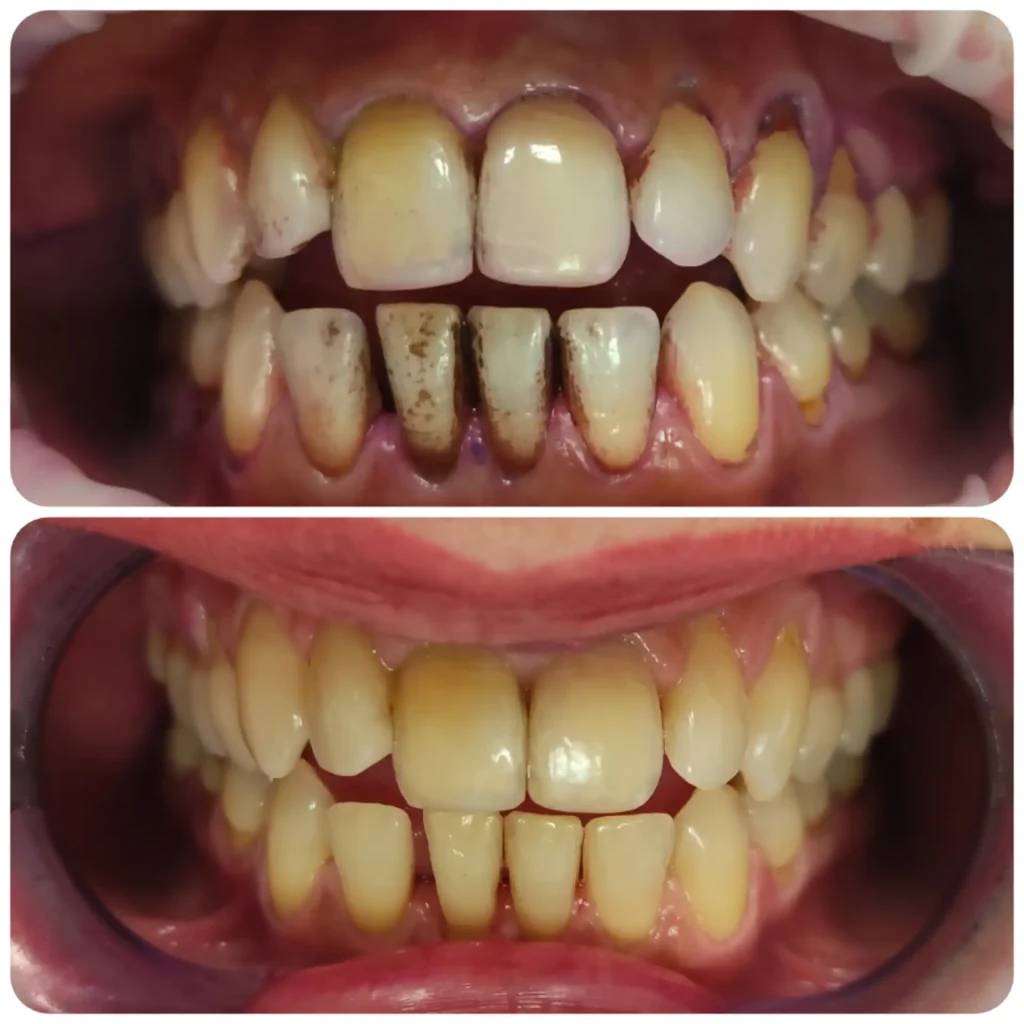

Fő érdeklődési területeim közé tartoznak az esztétikai beavatkozások, tömések, könnyebb gyökérkezelések, hagyományos fogpótlások készítése, kivitelezése. Fontosnak tartom a fogak megfelelő rehabilitációját és szájban tartását. Tudásomat hazai és külföldi szakmai továbbképzésekkel folyamatosan fejlesztem.

Célom a páciensek nyugodt, fájdalommentes kezelése. Igényeik, a lehetőségek maximális kihasználásával történő ellátása, melyet részletes tájékoztatással és a munkafolyamatok elmagyarázásával egészítek ki. Elengedhetetlennek tartom a kölcsönös bizalom kialakítását. Kezeléseim során a precíz, pontos végeredményre és a páciens teljes elégedettségére törekszem.